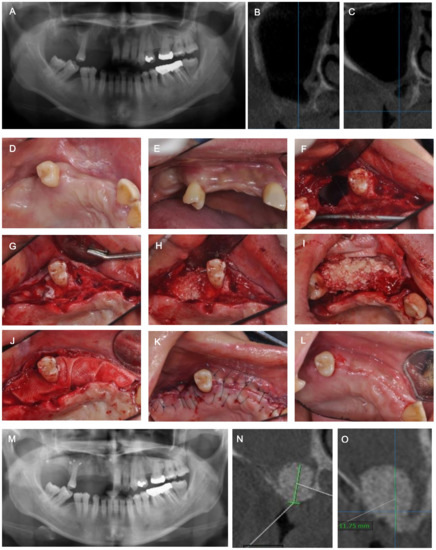

Implant Placement after Closure of Oroantral Communication by Sinus Bone Graft Using a Collagen Barrier Membrane in the Shape of a Pouch: A Case Report and Review of the Literature

2. Case Description